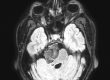

Η μαγνητική εγκεφάλου ανέδειξε ευμεγέθη αραχνοειδή κύστη δεξιά κροταφικά με σημαντική πίεση επί του υγιούς εγκεφάλου και παρεκτόπιση των δομών της μέσης γραμμής (έμμεση ένδειξη αυξημένης ενδοκράνιας πίεσης).

Στη συγκεκριμένη περίπτωση όμως η κύστη ήταν εξαιρετικά μεγάλη και πίεζε σημαντικά τον παρακείμενο εγκέφαλο. Αυτό φαίνεται ξεκάθαρα από τη λεγόμενη “παρεκτόπιση των δομών της μέσης γραμμής”. Αυτό σημαίνει ότι ο εγκέφαλος πιέζεται από τη μία μεριά τόσο πολύ, που οι φυσιολογικές εγκεφαλικές δομές παρεκτοπίζονται. Επιπλέον, η αυξημένη ενδοκράνιος πίεση προκάλεσε οίδημα στα οπτικά νεύρα, γι’ αυτό και η ασθενής είχε προβλήματα με την όρασή της.